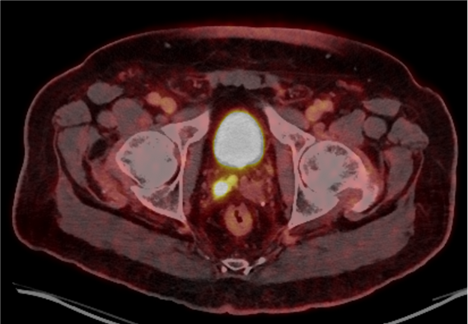

PSMA PET/CT demonstrated persistent uptake in the right posterior mid-gland and new uptake in the right SV, without nodal or distant disease (Figure 1). Multiparametric MRI (mpMRI) confirmed recurrent tumor involving the right SV and right vas deferens (Figure 2).